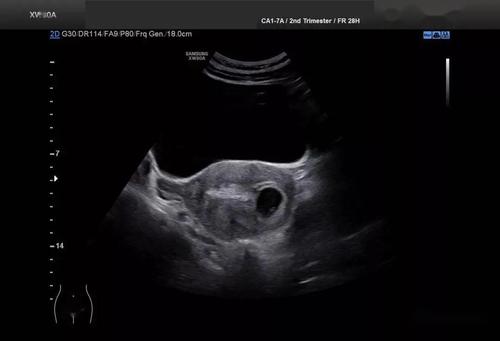

宫角妊娠超声诊断图片

宫角妊娠超声诊断图片,宫角妊娠彩超诊断图片

宫角妊娠彩超诊断图片

宫角妊娠b超图片高清

宫角妊娠b超图片

早期宫角妊娠b超图